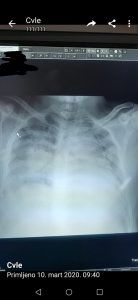

– Reč je o Influenci A, sezonskom gripu. Imao je srčanu slabost i slabost pluća. On je 10 dana osećao slabost organizma, mi smo u subotu insistirali da on bude hospitalizovan, na šta je pristao posle podne. Prebačen je na koronarnu jedinicu i nažalost preminuo je – rekao je za medije direktor Sazdanović. Hirurg Vladimir Đorđević iz Kragujevca objavio je fotografiju pluća preminulog pacijenta sa razlikom od jednog dana, kako bi ukazao na opasnosti virusa gripa i kako bi apelovao na građane da se ne leče „rakijom i belim lukom“. Iako još uvek nisu stigli rezultati obdukcije koji će potvrditi da je u pitanju običan virus, pluća pacijenta su ista kao kod osoba koje su preminule od korona virusa – tvrdi ovaj doktor.

– Nema šta da se objašnjava, ne mogu ovde da držim kurs medicine. Razlika je toliko upadljiva, zato sam okačio kao razglednicu posebno za one što se leče rakijom i belim lukom – napisao je dr Đorđević na Tviteru priznavši da je možda napravio propust što je tako nešto okačio, ali evidentno iz pametnih i opravdanih razloga. Kako i sam kaže slika preminulih od gripa i od korona virusa je ista. – Radi se o preminulom mladiću (25) u nedelju u Kragujevcu, navodno običan grip. Svrha tvita je da ukaže zašto su na respiratoru. I slepac vidi razliku, ne trebaš biti lekar. Isti bolesnik, razlika jedan dan – zaključio je. Prof. dr Predrag Sazdanović je dodao da je „pacijent 1995. godište i da je u nekom periodu kao vozač išao po auto-delove u Sloveniju“. Sazdanović naglašava da je Institut Torlak potvrdio da je pacijent imao sezonski grip, Influencu A, kao i da će uslediti obdukcija preminulog.